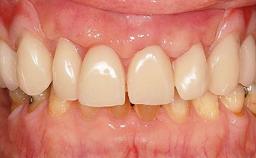

Fixed and removable prosthodontic implant therapy for restoration of the edentulous maxilla is both complex and challenging. Careful assessment and planning is needed in each individual case to explore whether a fixed or a removable solution will be the more suitable to satisfy the patient’s preference for optimal esthetics, phonetics, comfort and function. This Learning Pathway explores the prosthodontically driven treatment planning based on structured assessment, considered diagnosis and practical application in clinical case examples.